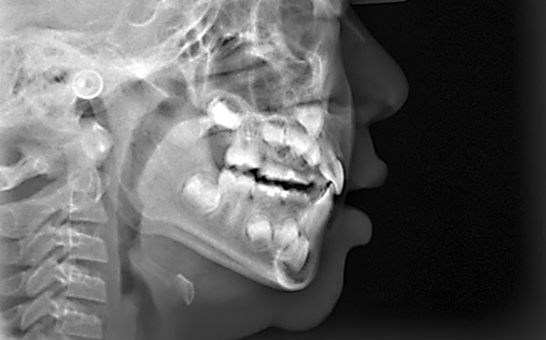

디지털 기반의 시뮬레이션 진단 과정을 통해 치아의 배열, 턱 관절 상태,

교합 상태를 정밀히 분석 후 교정 치료 계획을 수립하여 복잡한 케이스,

어려운 고난도 케이스도 전문적인 교정 치료가 가능합니다.

실시간 3D 데이터 분석을 통해 교정 전/후의

예상 결과를 시각적으로 빠르게 확인이 가능합니다.

단순히 치아 배열만 보는 것이 아니라, 교합 상태, 치아 마모,

교정 필요성까지 정밀 분석이 가능합니다.

치아와 교합 상태를 정밀하게 분석하여

환자에게 맞는 인비절라인 치료 설계가 가능합니다.